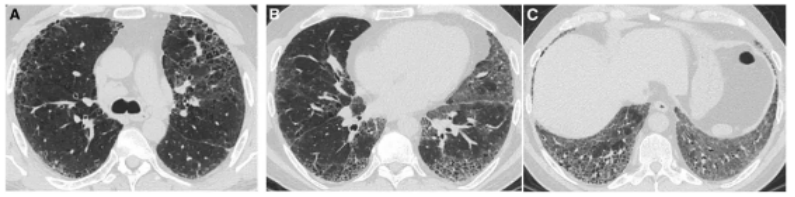

图:(从左至右)急性、亚急性、慢性

1、所谓急性HP,就是患者接触了较高水平的暴露,例如有患者喜欢饲养鸟类,尤其喜欢宠物鸽子,于是到交易市场去看,在这个过程中,可能出现了间断高水平暴露,于是一些易感个体就在很短的时间内(4到12小时)出现了流感样症状和呼吸道症状,而肺内则出现了一些磨玻璃影。

2、也有一些患者急性发作伴发热,劳力性呼吸困难、乏力和咳嗽,影像表现为小叶中央性的弥漫性的腺泡结节,称之为亚急性HP

3、还有些患者持续性低水平暴露,起病很隐匿,当我们发现时,已经出现了劳力性呼吸困难,干咳,体重减轻和乏力,而影像出现了既有磨玻璃影,也有肺纤维化的表现,称之为慢性HP